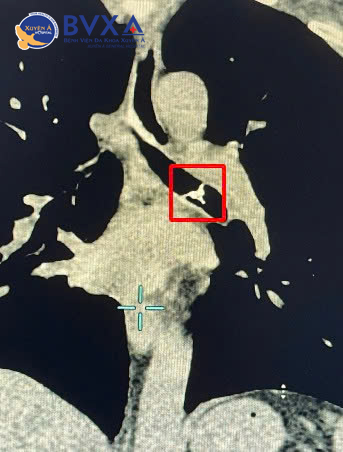

Tại đây, các Bác sĩ phòng khám chuyên khoa Hô Hấp đã khám và nhận định trường hợp này nghĩ nhiều đến viêm phổi do hít sặc hoặc dị vật. Bệnh nhân được chỉ định chụp CT-scan lồng ngực thì Kết quả cho thấy một dị vật cản quang nằm trong lòng phế quản gốc trái – vị trí cực kỳ nguy hiểm vì chỉ cần thêm một chút di chuyển, mảnh xương có thể đâm thủng phế quản, gây biến chứng nặng.

Hình ảnh CT cho thấy mảnh xương cá